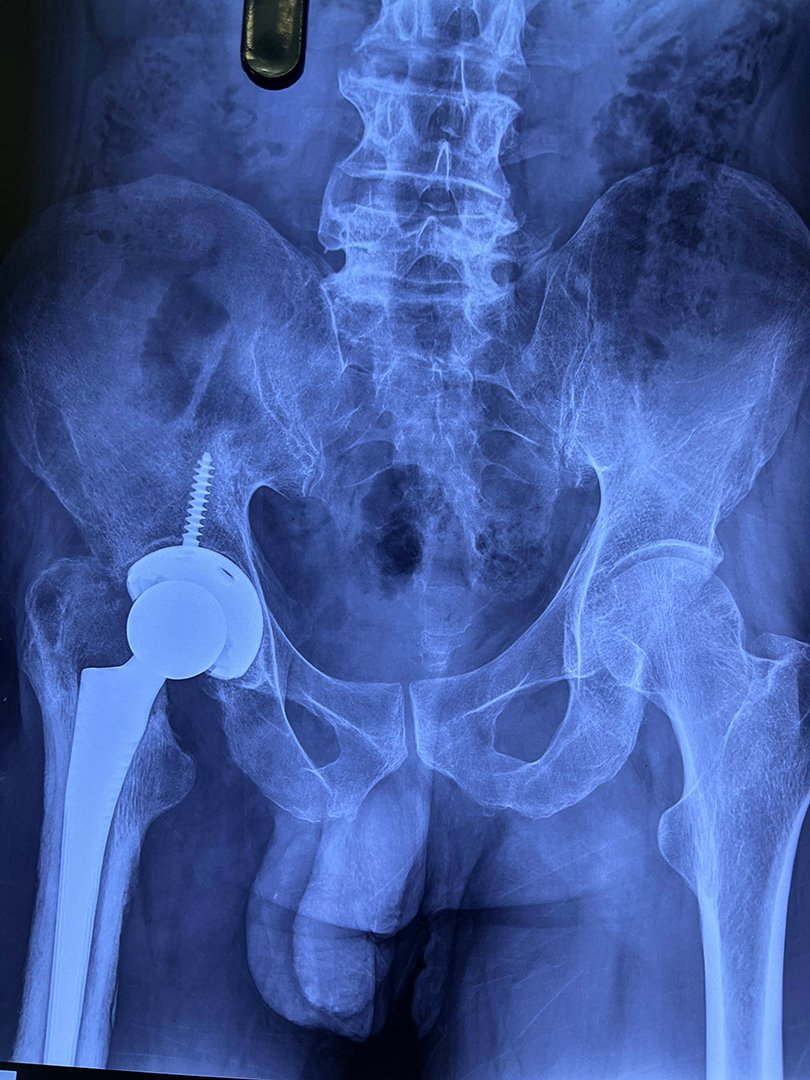

Post-Op - Stage 2 Long Stem THR